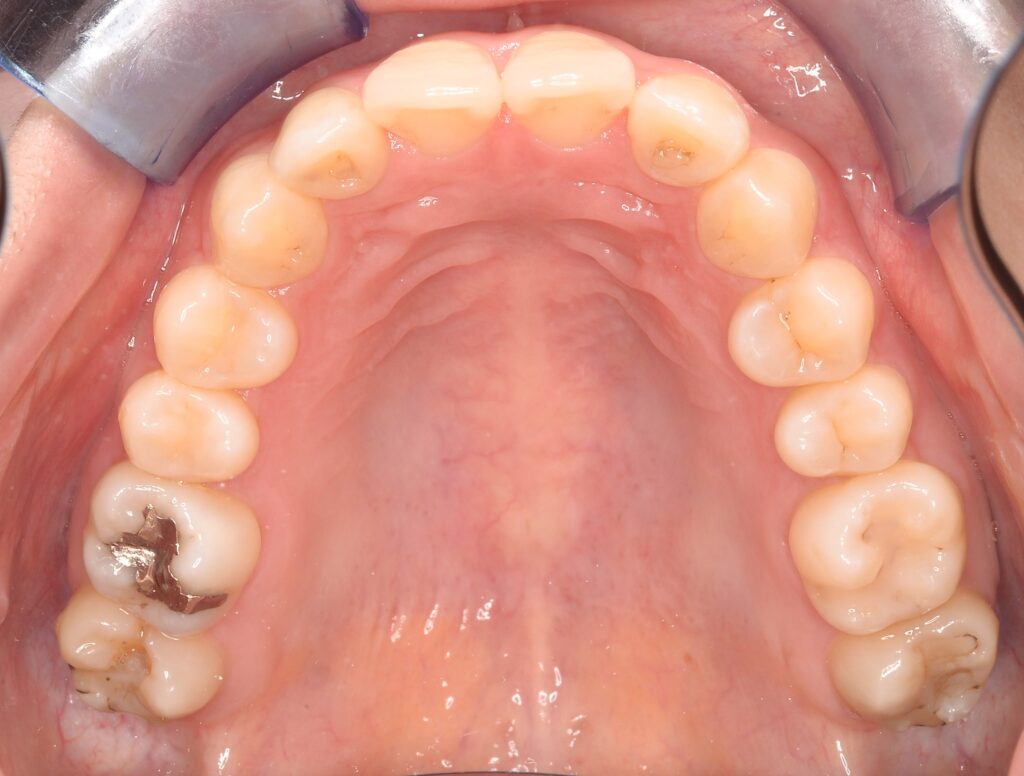

本日は以前から歯並びが気になっていた方のマウスピース矯正の患者様を紹介させて頂きます🍀

26歳・女性

主訴:歯並びが気になる

治療方法:マウスピース矯正(IGO)

治療費用:¥498,000+税 ※別途検査代、再診料あり

治療期間:11ヶ月

リスク・副作用:マウスピースの装着時間が少ないと治療期間が長引く可能性あり。

また、適切な保定をしないと治療後に後戻りすることもある。

《Before》